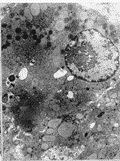

內毒素與腫瘤壞死因子作用24h後,均可使體外培養肝細胞超微結構受損,表現為糖原減少,溶酶體增多,線粒體腫大,嵴溶解,內質網擴張及斷裂,甚至可見核空泡化,染色質消失,其中以腫瘤壞死因子引起的肝細胞損傷為重,若二者聯合作用,則肝細胞受損更加嚴重(Fig1~6).

壞死毒素圖1 LPS作用後肝細胞內質網、線粒體腫大

fig1 SwellingofmitochondriaandendoplasmicreticuluminculturedhepatocytesinducedbyLPS ×5000